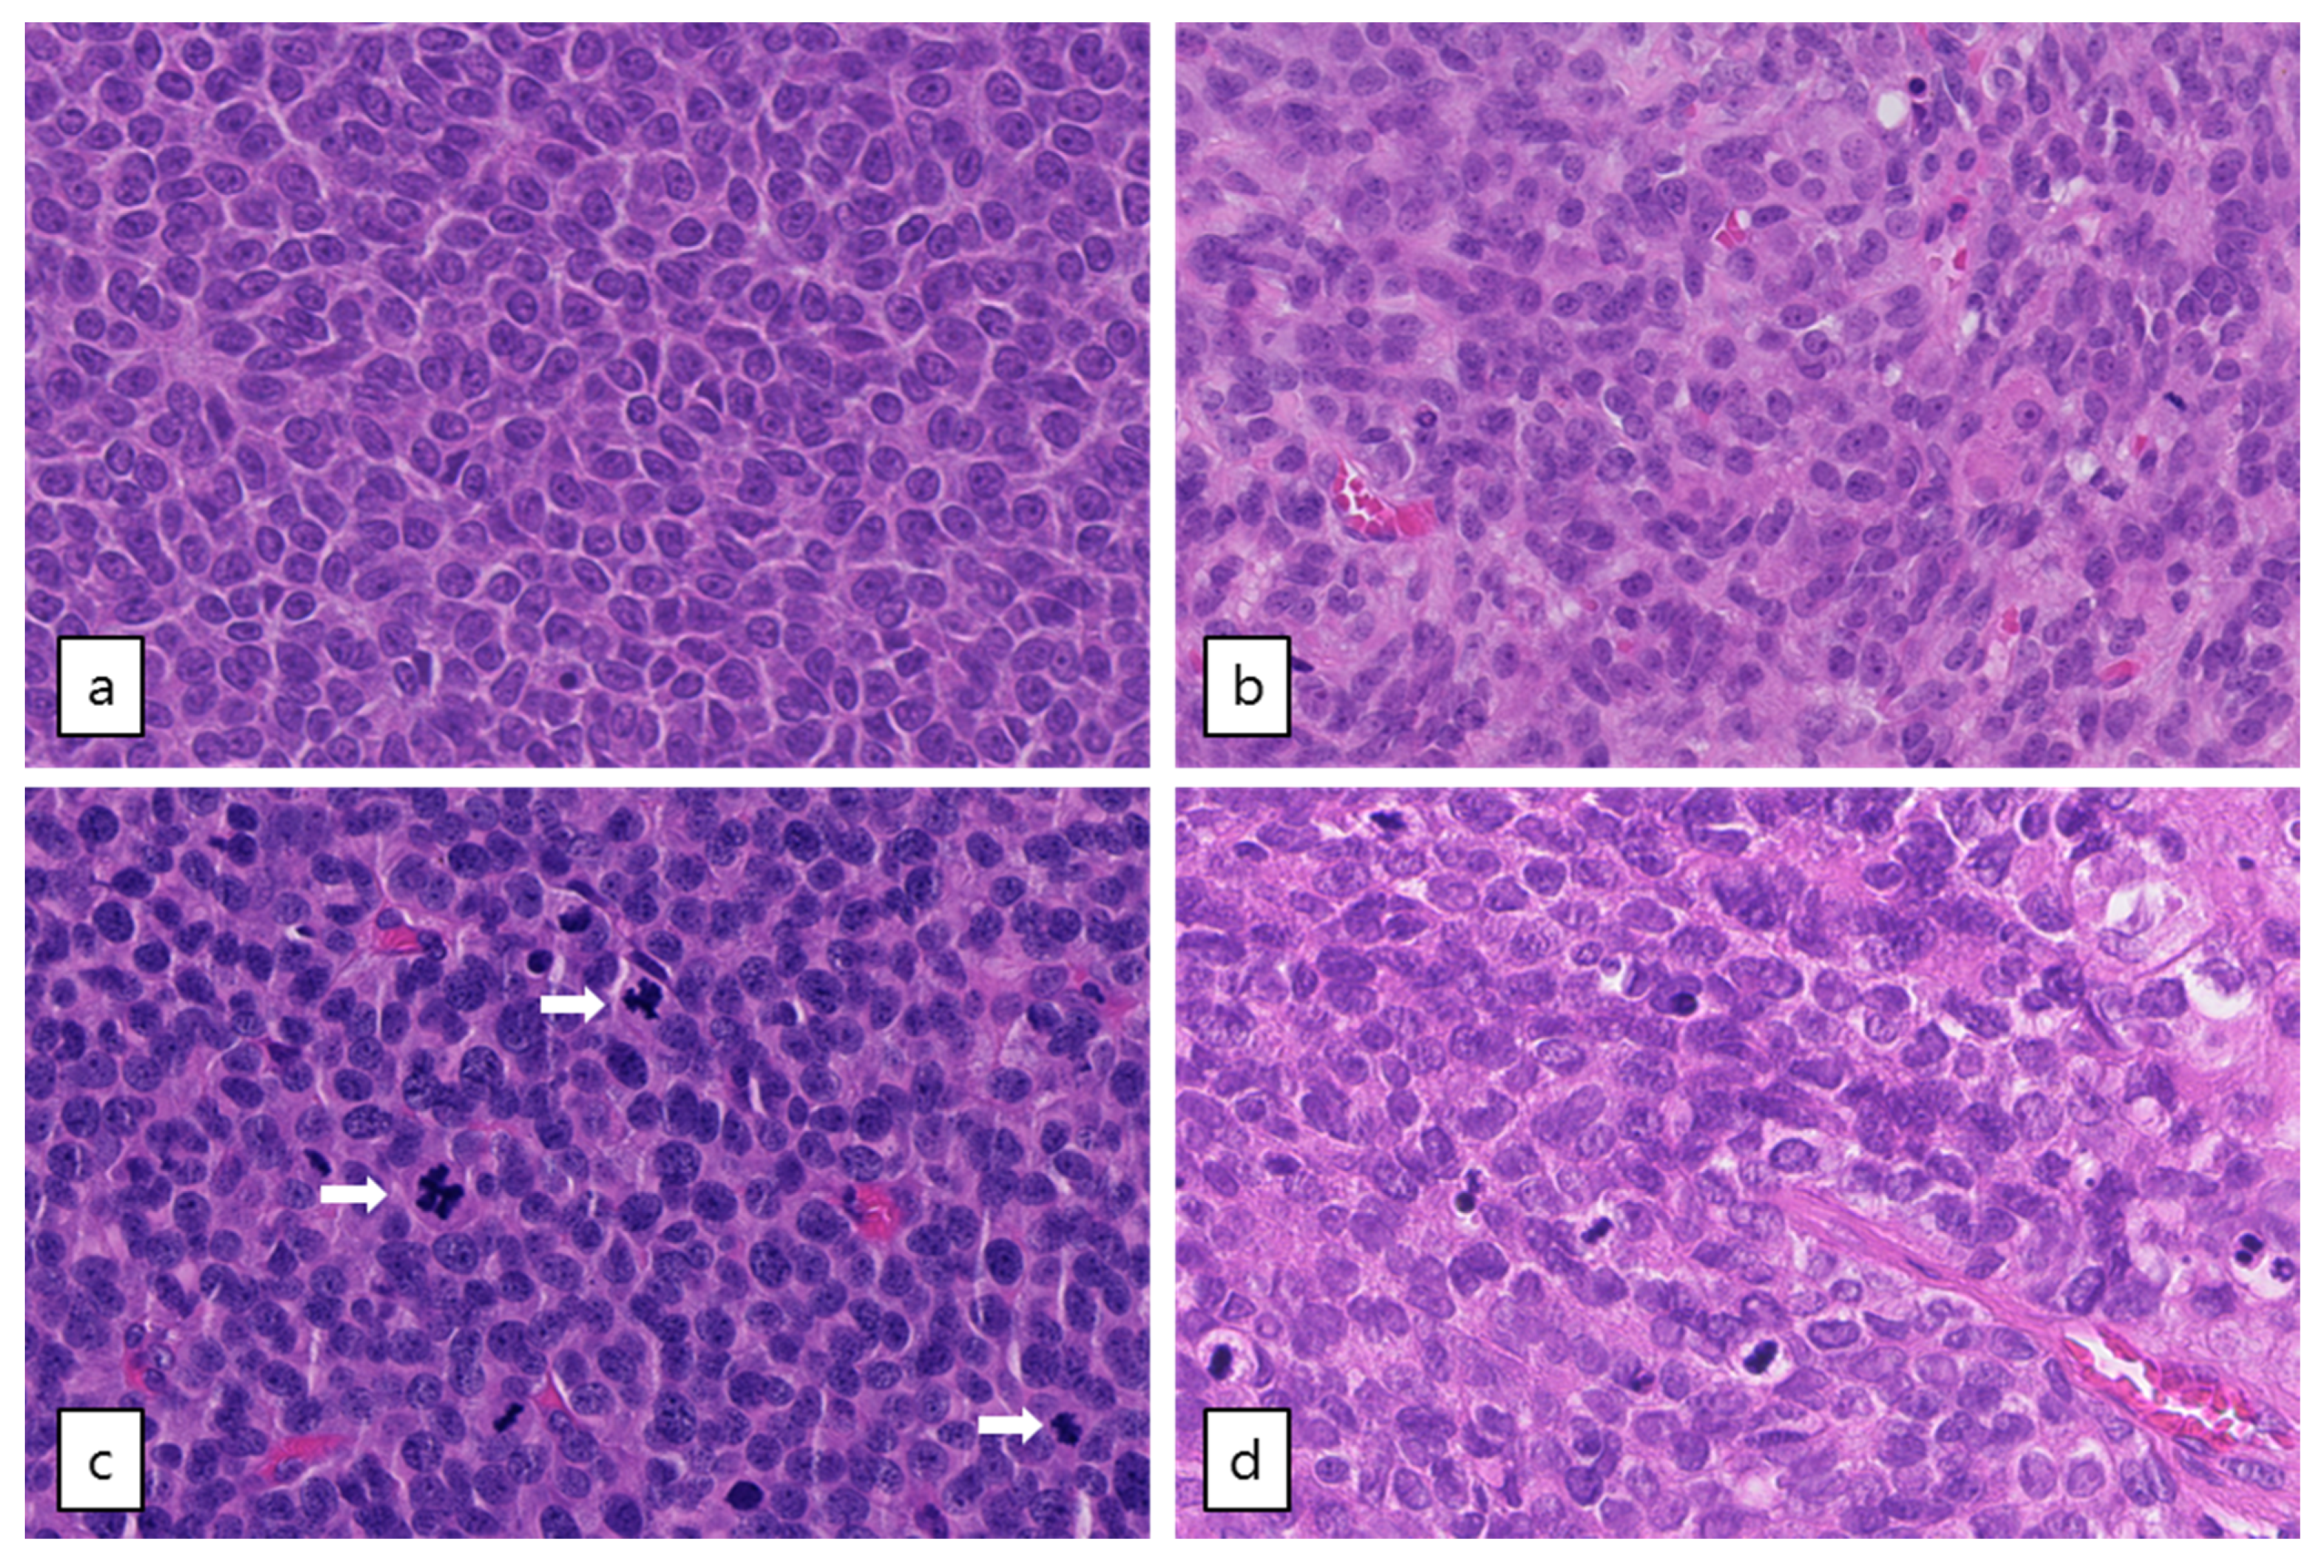

Out of the five patients with the highest mutational load, three had a TP53 mutation combined with loss of heterozygosity (R248G, H179R and C135Y, respectively, Figure 2). These tumors harbored numerous copy number alterations, and increased mitotic activity was seen on hematoxylin and eosin (H&E) slides from two patients (18 and 70 per 2 mm2, respectively) as compared to TP53-wildtype patients (range 2–12 per 2 mm2) (Figure 3). The TP53 mutant tumors harbored a higher number of both SNVs (median 12,027, range 7100–21,452) and SVs (median 188, range 66–314) as compared to the TP53-wildtype tumors (median 3336 SNVs, range 1346–9211, median 20 SVs, range 0–120, Figure 2c, Figure 4 and Figure S3a). Notably, none of the TP53 mutant samples harbored a TERT promotor mutation, which is detected in 41% of recurrent AGCTs. These mutually exclusive alterations may indicate a different molecular mechanism for disease progression.

Figure 3.

Microscopic examination of AGCTs. H&E staining of adult type granulosa cell tumors showing a homogenous cell population with typical grooved, coffee bean-like nuclei. (a) Tumor GCPA011T1.1 with FOXL2 mutation (20× magnification). (b) Tumor GCPA021 (with TERT C228T mutation, DICER1 E1813D and DICER1 stop-gain variant Q1230 *, 20× magnification). (c) and (d) Tumors GCPA016 and GCPA002 with pathogenic TP53 mutation (H179R and C135Y, respectively, 20× magnification). Mitotic activity is indicated by arrows.